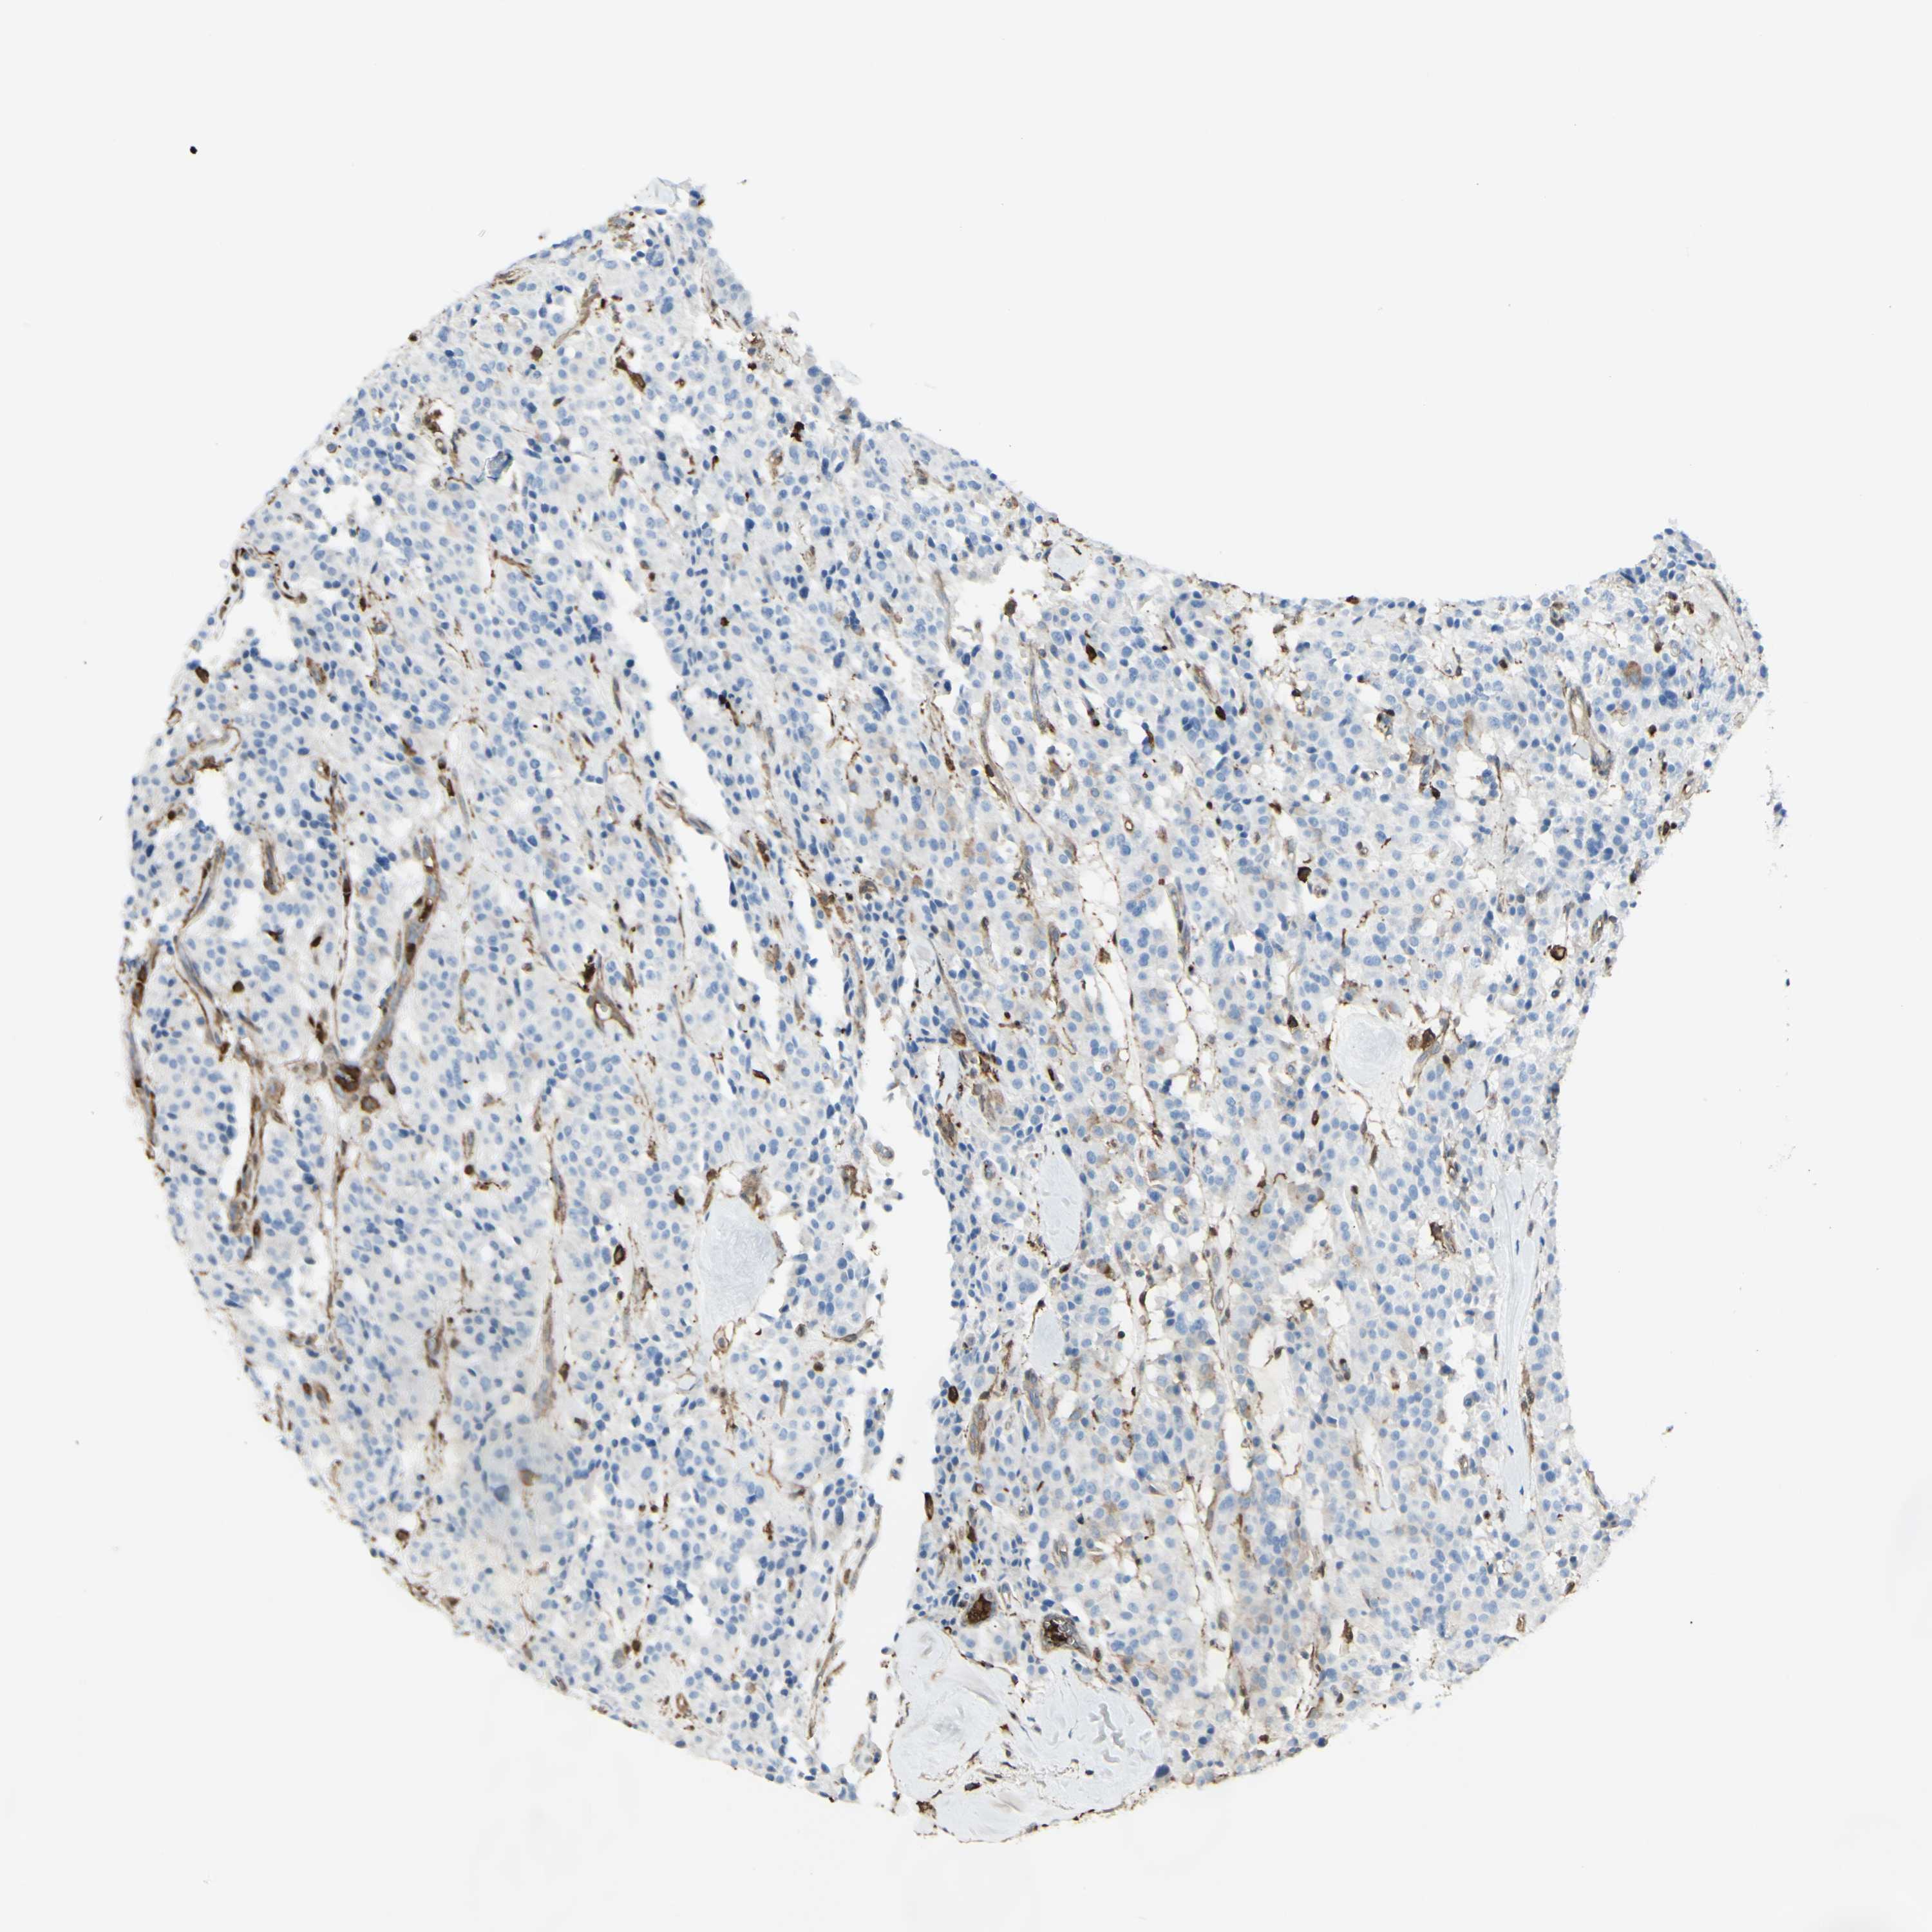

CARCINOID - Protein expressioni

A mouse-over function shows sample information and annotation data. Click on an image to view it in a full screen mode. Samples can be filtered based on level of antibody staining by selecting one or several of the following categories: high, medium, low and not detected. The assay and annotation is described here.

Each image is clickable and will lead to virtual microscopy that enables deeper exploration of all samples and also displays staining intensity scores, fraction scores and subcellular localization as well as patient and tissue information for each sample.

Antibody HPA054026

Staining

High

Medium

Low

Not detected

Carcinoid, malignant, NOS